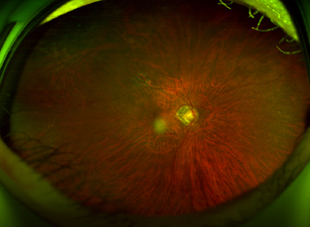

수술 전 사진

Before Surgery

수술 후 2일 사진

2 Days Post-Op

(Air 80%)

수술 후 7일 사진

7 Days Post-Op

(Air 30%)

수술 후 10일 사진

10 Days Post-Op

(Air 0%)